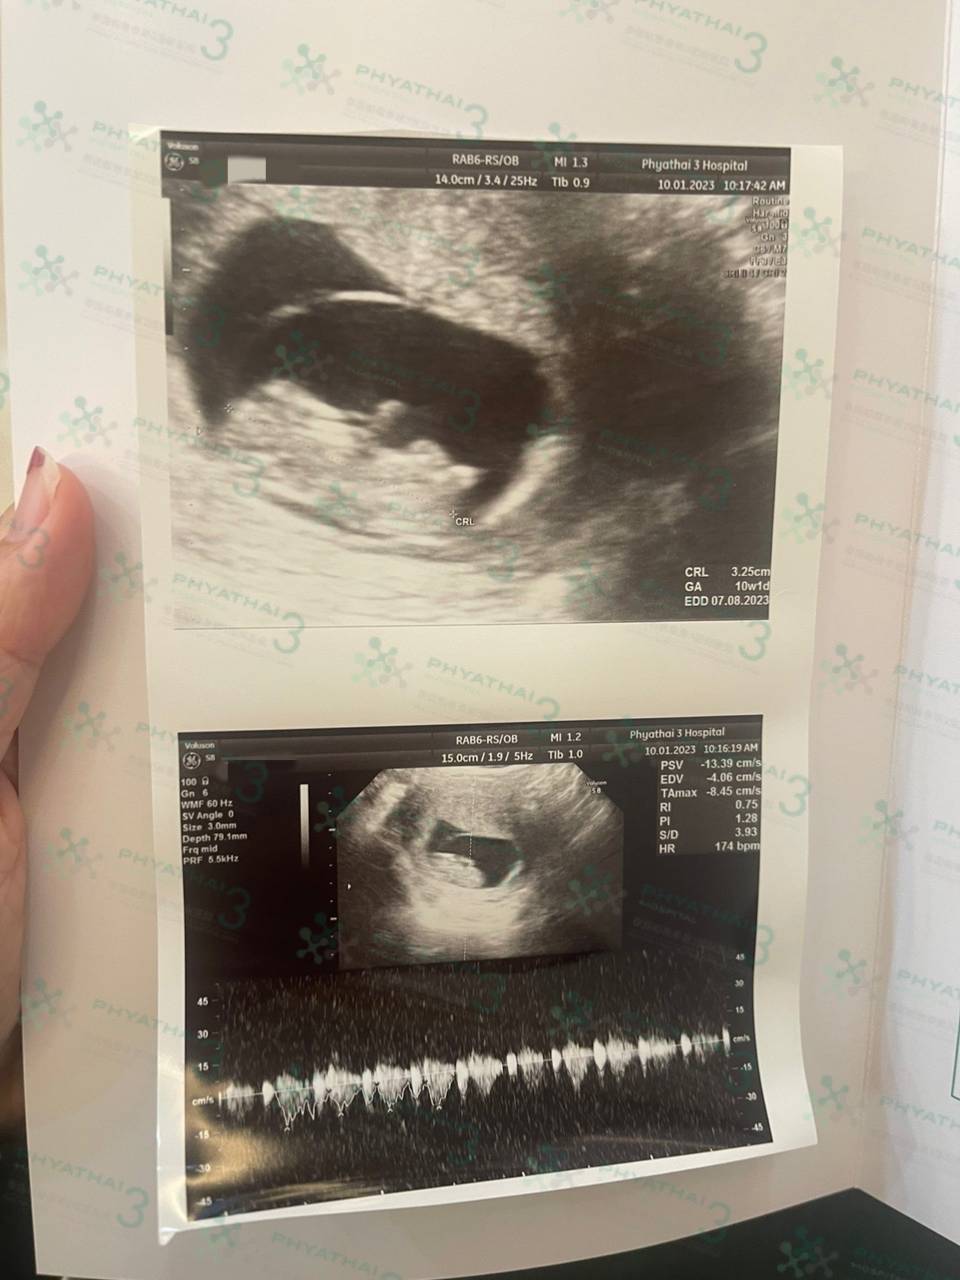

孕期第九周,看看这个活泼好动的小宝宝是多么调皮呢。今天我们患者已经孕期第九周啦,而且也是我们患者第一次能够那么清楚看到宝宝的手和脚,今天看到我们的手和脚还疯狂在孕囊里面拳打脚踢,感受到真奇妙,虽然还是一个小豆芽但是已经会活动了,而且我们医生也说宝宝真的很好动,从小就是那么调皮活泼呢~~因为之前出差一直没有看到宝宝真面目的爸爸今天也感觉真的是很幸福,幸福的三口之家一路绿灯好运连连吧